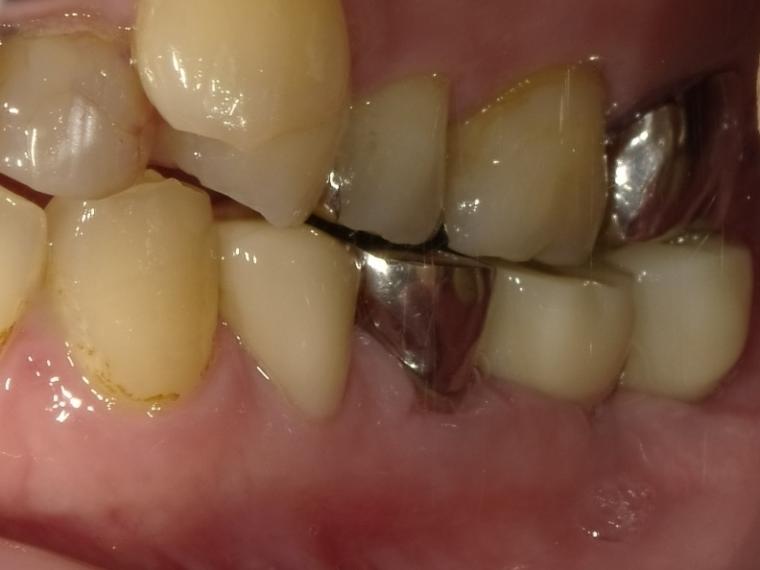

AFTER

第一大臼歯と第二大臼歯をインプラント、第二小臼歯をクラウンでの治療を希望されました。

現在も定期健診で拝見させていただいています。